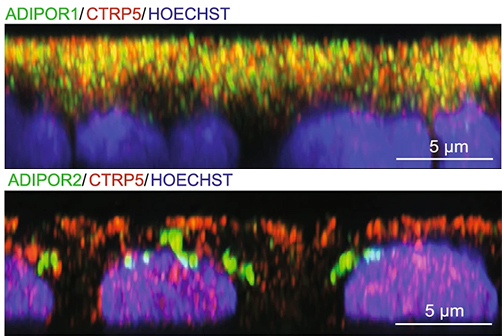

LSU Health New Orleans Researchers Discover a Key Failure in AMD that May Lead to Progression & Vision Loss

Research led by Nicolas Bazan, MD, PhD, Boyd Professor, Ernest C. and Yvette C. Villere Chair for the Study of Retinal Degeneration, and Director of the Neuroscience Center of Excellence at LSU Health New Orleans School of Medicine, suggests that age-related macular degeneration (AMD) decreases an essential fatty acid, preventing the formation of a class of protective molecules and reducing repair potential. The discovery may also open new therapeutic avenues for AMD. More

LSU Health Contributes to Research Suggesting Late-Onset Retinal Degeneration Mechanism & Potential Rx

A study led by the National Eye Institute (NEI) that included five researchers from the Bazan Lab at the LSU Health New Orleans Neuroscience Center of Excellence has discovered how late-onset retinal degeneration can develop and a surprising potential therapeutic -- metformin. The results are published online in Communications Biology, a Nature journal. More